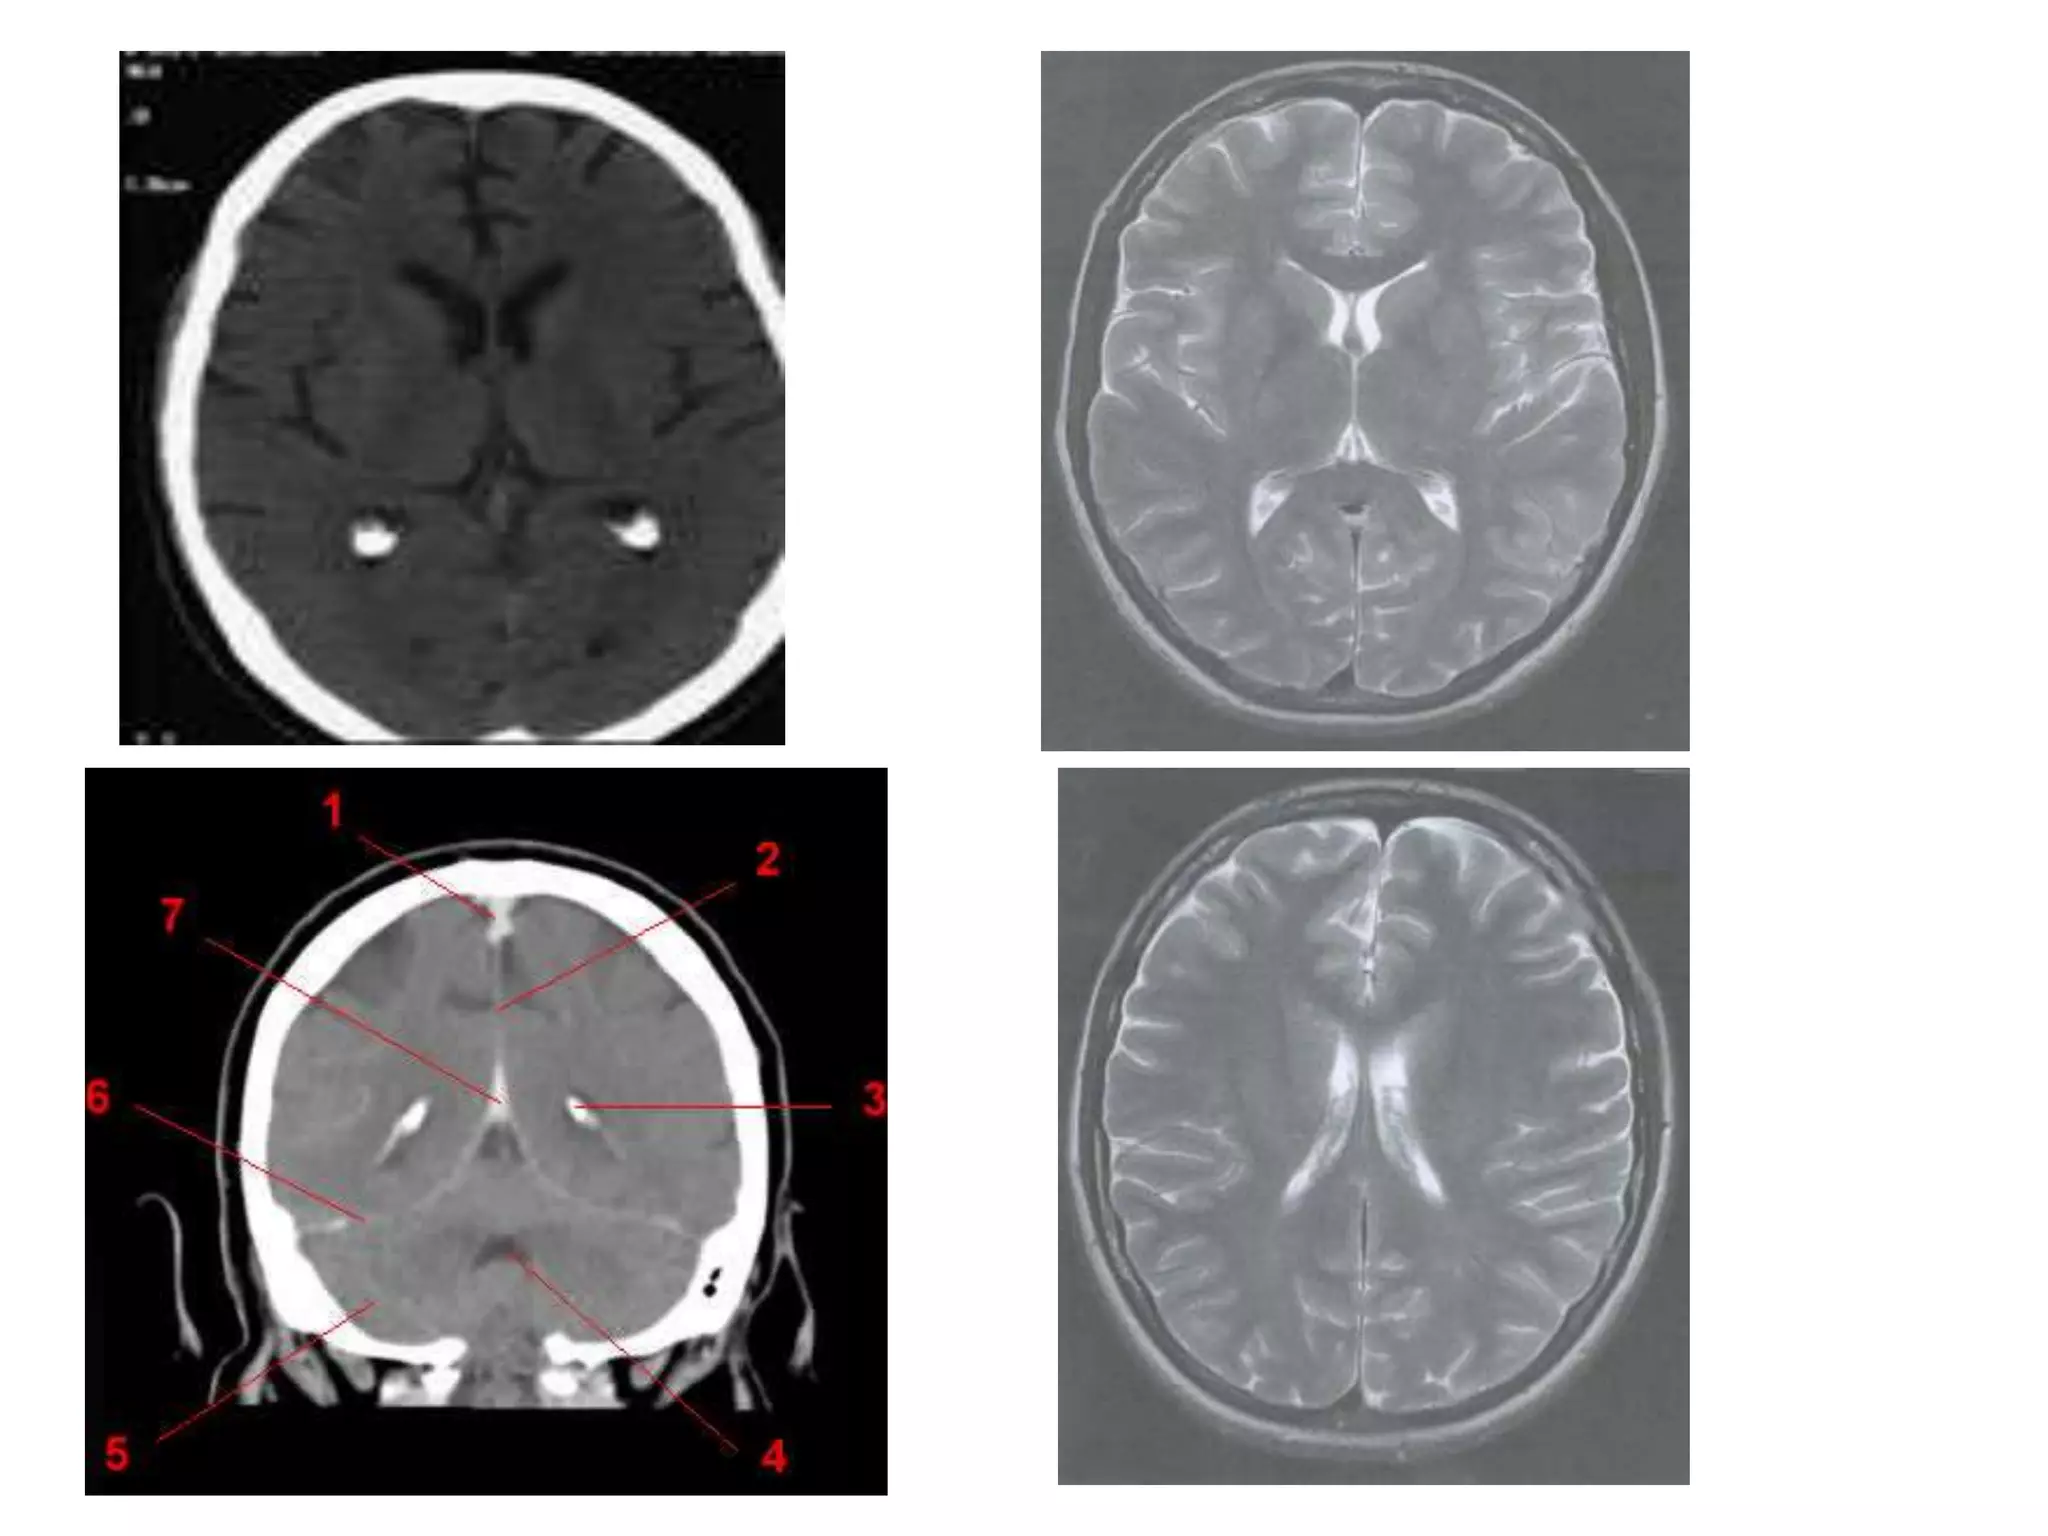

VENTRICULAR SYSTEM

   Lateral ventricles – Telencephalon ( cerebral hemisheres)

   3rd ventricle      – Diencehalon

   Sylvian aqueduct – Mesencephalon (midbrain)

   4th ventricle      – hind brain (pons+medulla)

• Saggital and Coronal T1 weighted MRI – accurate

assessment of ventricles and C. callosum

• Mid Saggital section – for shape and configuration

of Aqueduct of Sylvius.

• CSF intensity on MRI

Lateral ventricle

• Parts :

Horns – Frontal, Occipital and

Temporal.

Body

Trigone / Atrium

• Relations :

supr. – C. callosum

infr. – choroid plexus, thalamus

and hippocampus

lat – caudate nucleus

med – S. pellucidum and fornix

Septum pellucidum : seperates lateral ventricles (FH and

body).

• It is a midline triangular sheet attached above to

C.callosum and postr.ly to fornix.

• It has 2 laminae with narrow cavity.

( cavum SP – due to seperation of 2 laminae. In 10% adults )

• Radiology –

Axial MRI / CT : frontal horns separated by

S. pellucidum and posteriorly lateral ventricles diverge

and pass into temporal and occipital horns.

Saggital MRI : ‘C’ shaped , curving round the

thalamus.

Coronal : frontal horns – inverted triangle

body – flattened

temporal horns – like ‘C’ on its sides.